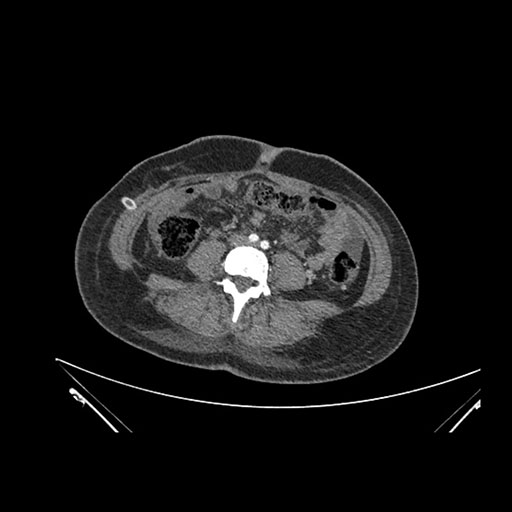

Axial Arterial

Axial Venous

Imaging analysis

Based on initial findings, which issue(s) would you be most concerned about?